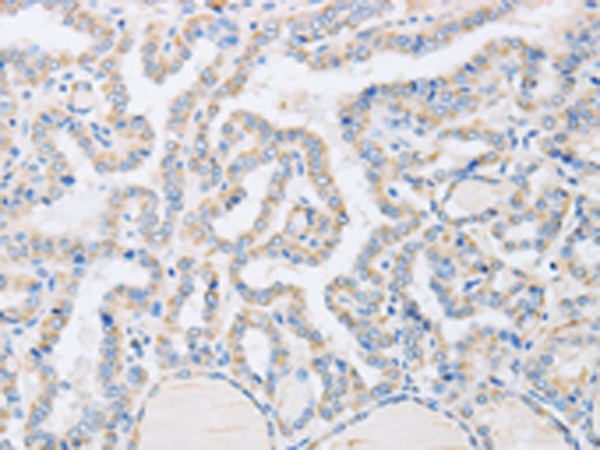

分类: 科研抗体货号: P00883别名: ADH1应用: IHC反应种属: Human